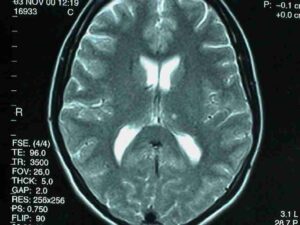

Thalamusinfarkt